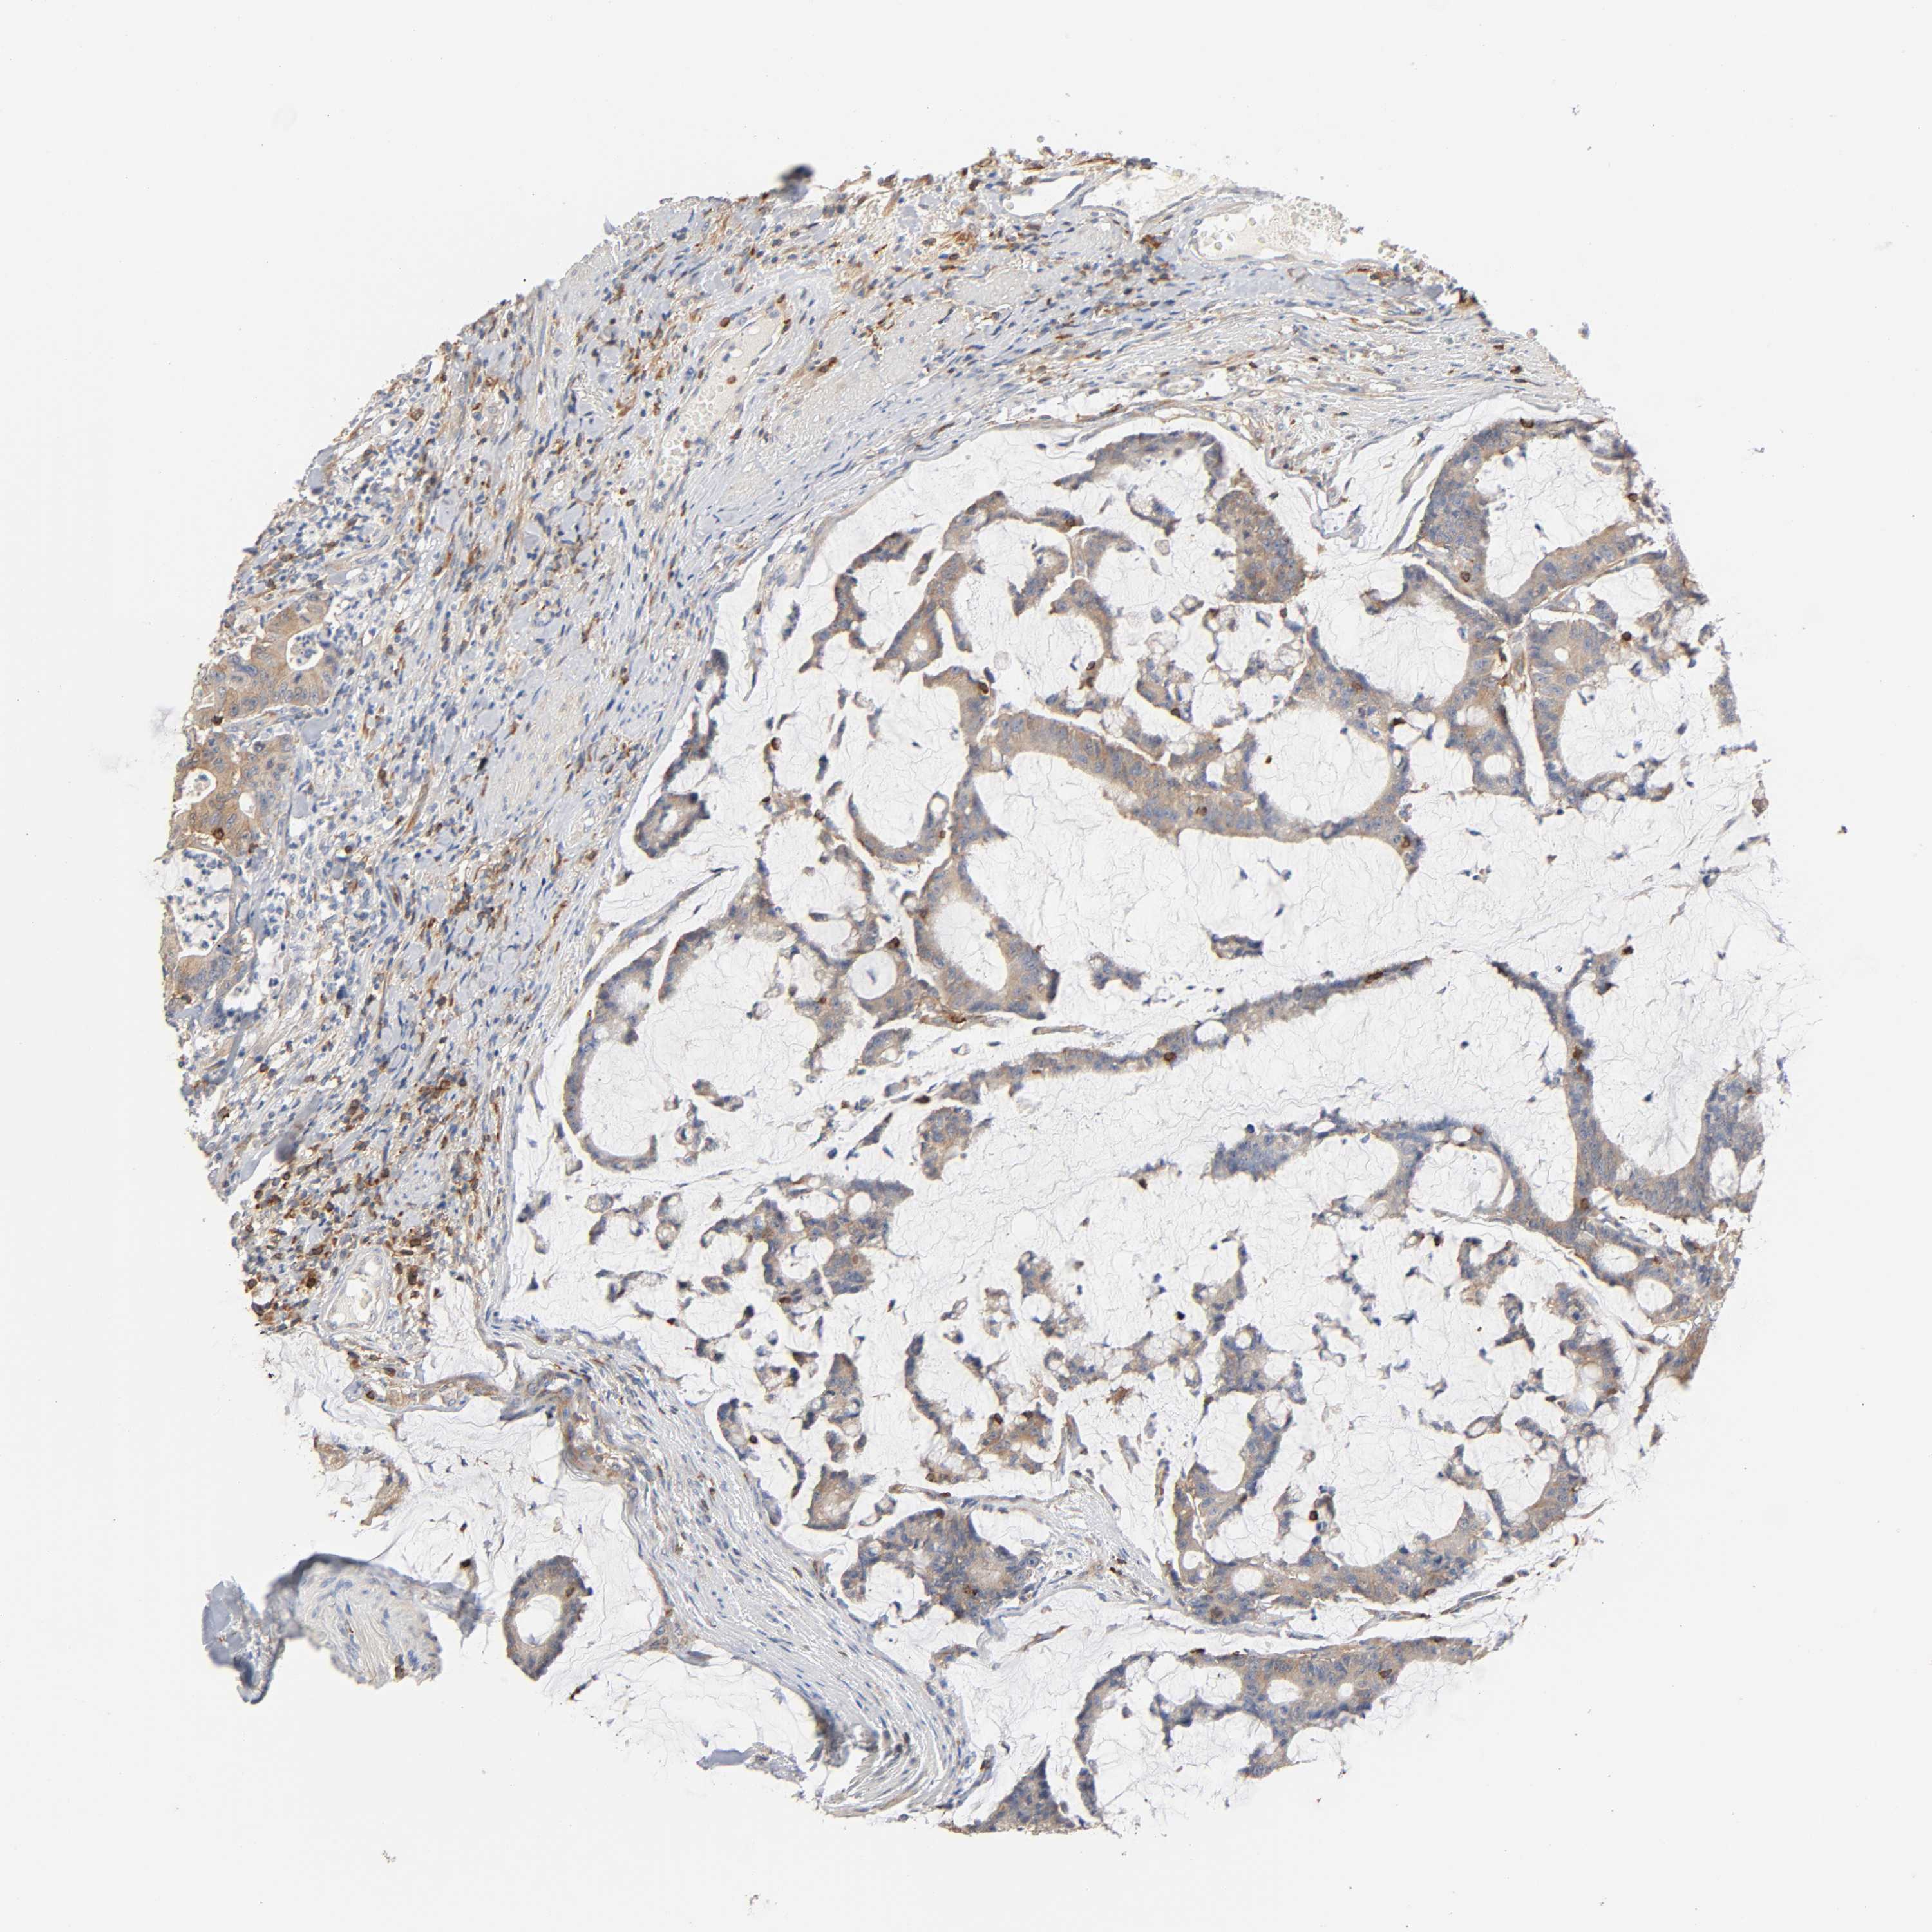

CANCER COLORECTAL CANCER Show tissue menu

COAD TCGA COAD VALIDATION READ TCGA READ VALIDATION PROTEIN COAD CPTAC PROTEIN EXPRESSION

ANTIBODIES

AND

VALIDATION